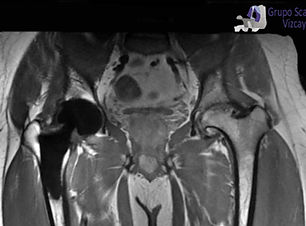

ARTICULACION COXO - FEMORAL

ARTRO DE CADERA

CADERA CONTRASTE

PELVIS